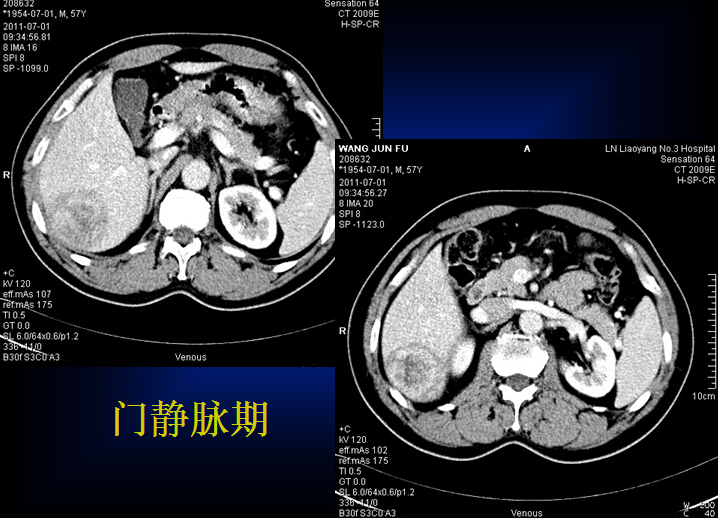

原发性肝癌的CT诊断